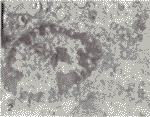

透射电镜下见治疗组肿瘤细胞细胞核染色质凝聚成团块,有的成典型的新月形改变,附于核膜下,有凋亡的改变(见插页第4页图2),而对照组肿瘤细胞核膜及细胞器结构完整,未检出有这种凋亡的特征性改变(见插页第4页图3)。

图2 透射电镜下治疗组肿瘤细胞,可见染色质凝聚于核膜下的凋亡改变

图3 透射电镜下对照组肿瘤细胞,未见细胞凋亡的特征性变化